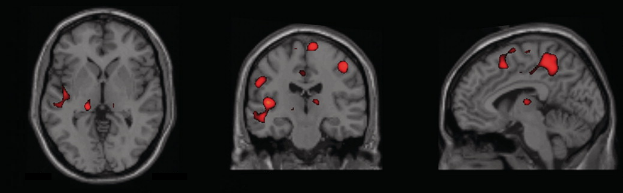

Atrofia multisistémica (AMS)

El paciente puede sufrir lentitud, rigidez y dificultades en el equilibrio o para caminar. También puede sufrir síntomas en el cerebelo (una parte del encéfalo que coordina movimientos musculares) como pérdida de equilibrio, o dificultades para hablar. Por último, puede afectar al sistema nervioso autónomo e interferir en tareas que el cuerpo hace automáticamente, como regular la presión sanguínea, vaciar la vejiga, etc.